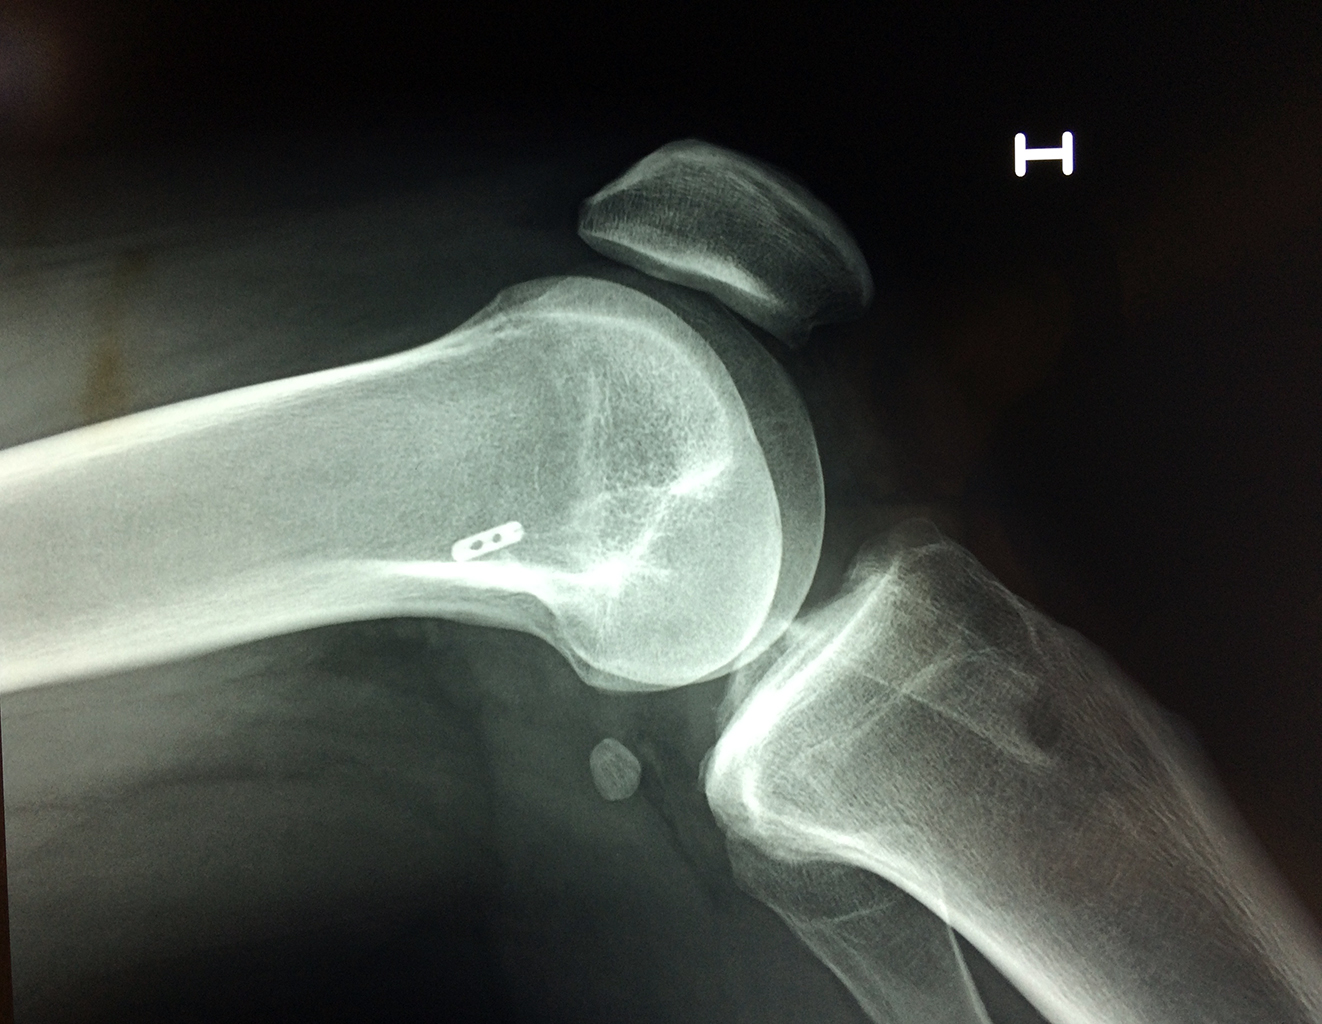

Cirugías de Húmero - Rodilla

La artroscopia de rodilla es un cirugía en el cual la estructura interna de la articulación es examinada ya sea para realizar un diagnostico o para realizar un tratamiento, este procedimiento se realiza utilizando un instrumento parecido a un pequeño tubo llamado artroscopio.